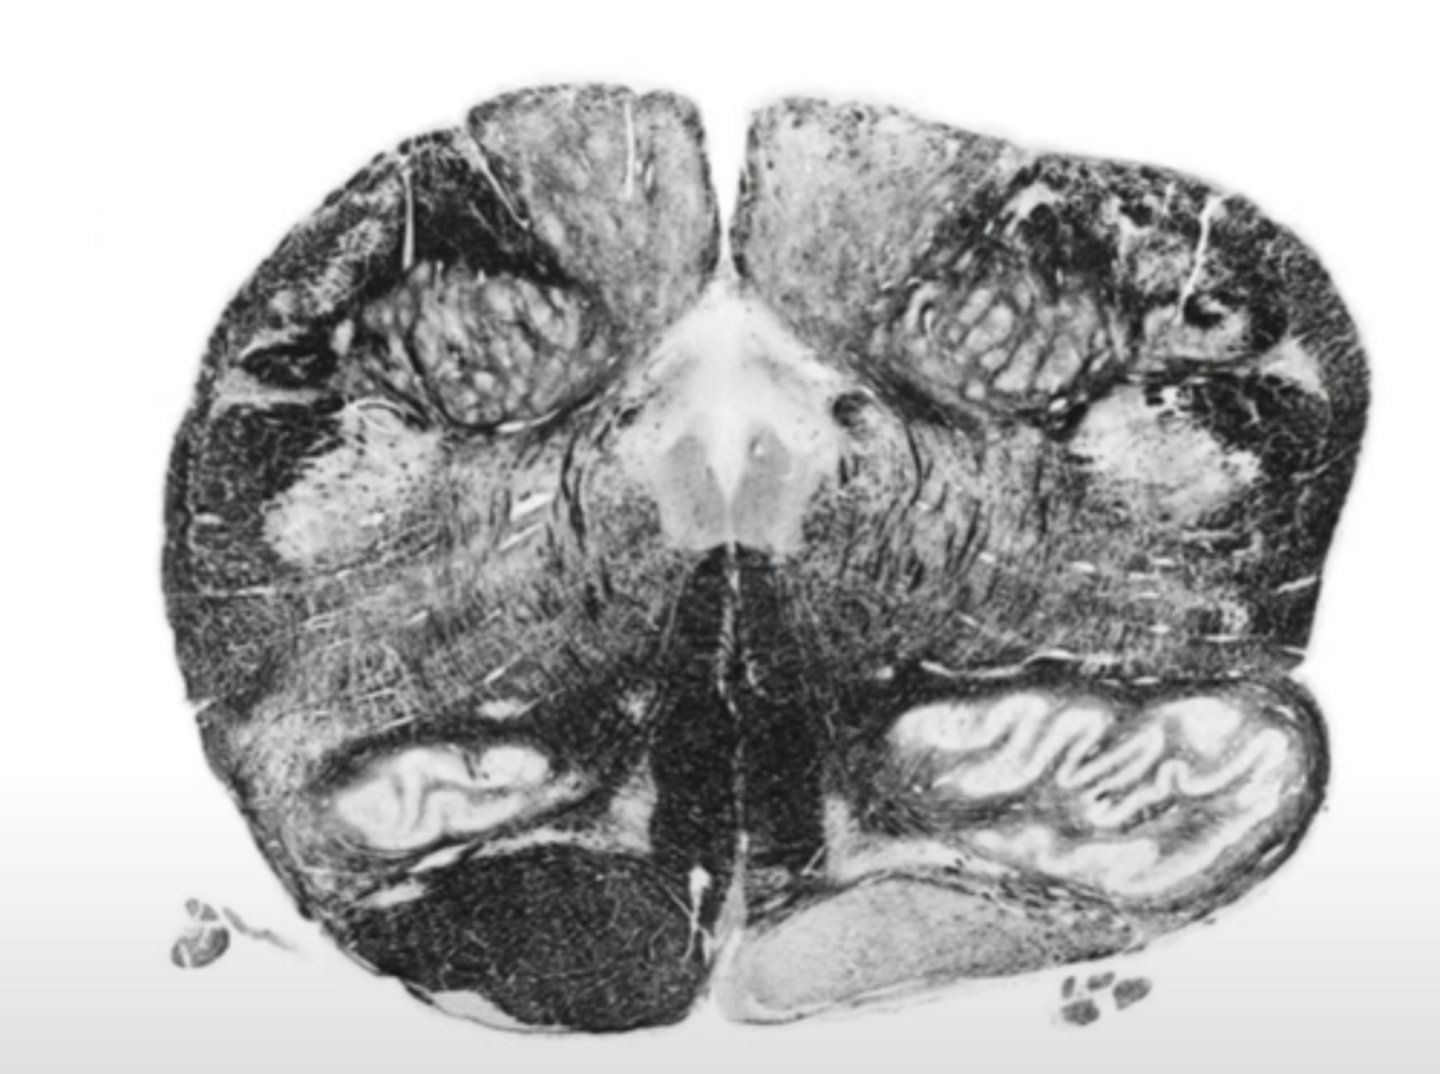

superior cerebellar peduncles

ID the structure

inferior cerebellar peduncles

fourth ventricle

ID the space

central gray

middle cerebellar peduncles

reticular formation

medial lemniscus

corticospinal fibers

pontine nucleus

ID the nucleus

vestibular nucleus

abducens nucleus

facial nucleus

facial nerve

ID the nerve